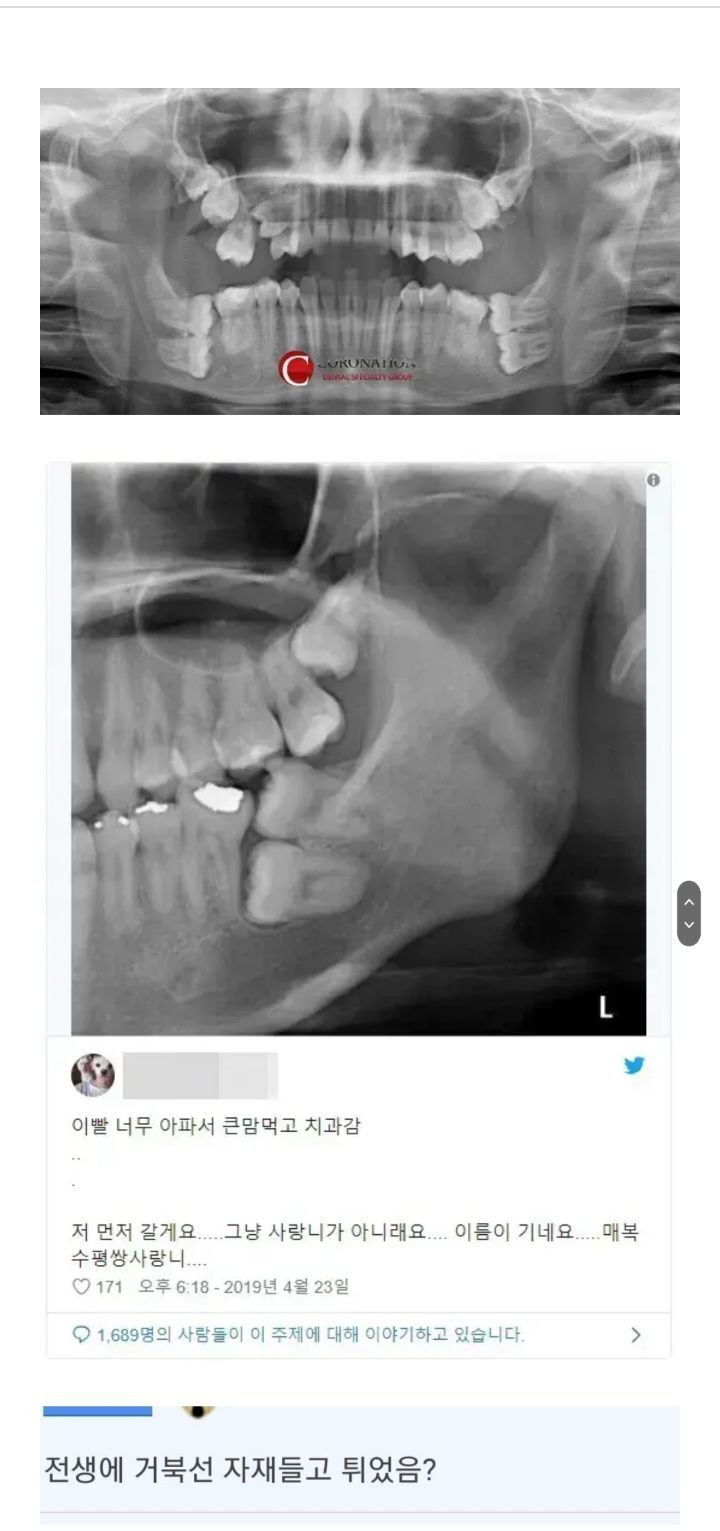

• 작성자표예진언니 | 작성시간 00:25 new 위는 둘 다 수월했고..아래 하나도 뭐 나름 ㄱㅊ 나머지 한놈이 안뽑혀서 아주 조각조각조각내서 건져냄; 거의 한시간을 뽑아서 중간에 의사가 잠시 입 닫고 쉬라고했어; 끝나고 졸라 부엇고

• 작성자~간주중~ | 작성시간 01:48 new 하나 뽑았는데 매복이라 개뒤질뻔 다른 사랑니 전부 매복이라 몇년째 손도 못대는중…